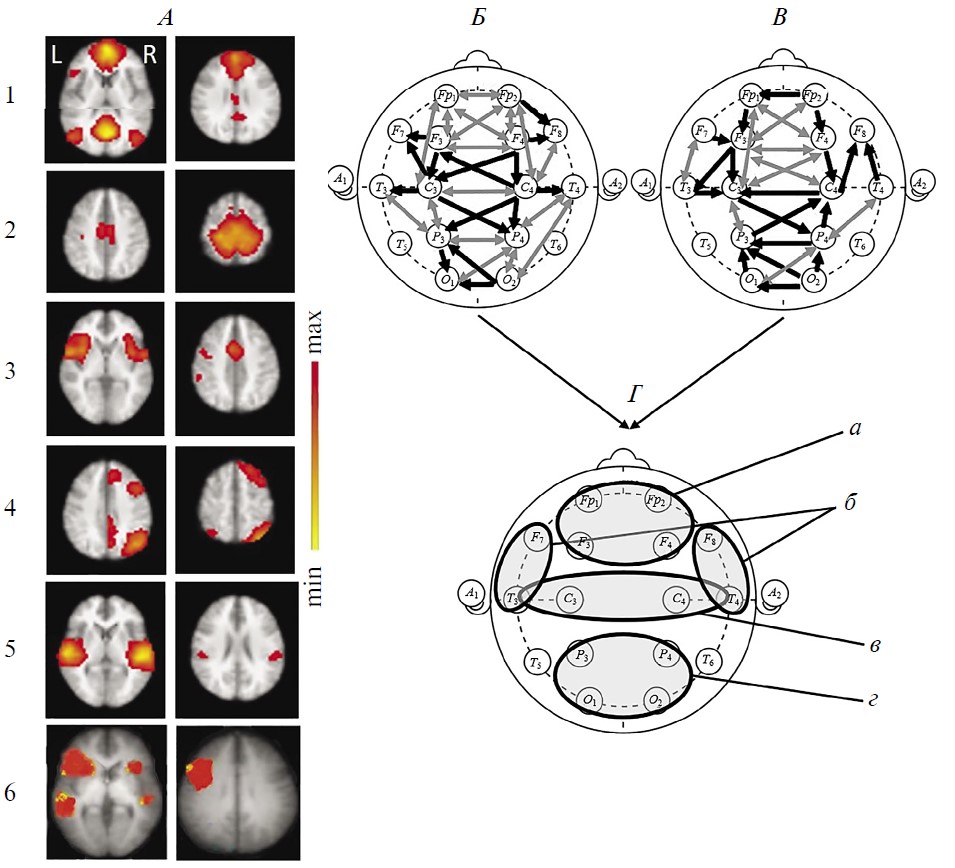

На рис. 2, I представлены изображения RSN фМРТ этого пациента (из числа перечисленных в методике), выявляемых до (рис. 2, I, А) и после рТМС (рис. 2, I, Б) на идентичных аксиальных срезах мозга. В первом исследовании, на фоне вегетативного состояния, удалось верифицировать компоненты лишь 3-х из 6 исследуемых RSN (рис. 2, I, A): DMN, cенсомоторной и слуховой. Однако эти сети резко отличны от нормы асимметричностью и фрагментарностью. В сети DMN доминирует левополушарный каудальный (затылочный) компонент при значительной редукции лобного. Сенсомотороная сеть представлена компонентами в глубинных отделах правого полушария. Слуховая — левосторонней активностью в базальных отделах.

Рис. 2. Динамика сетей покоя функциональной магнитно-резонансной томографии (фМРТ) и коннективности ЭЭГ-диапазона 1–15 Гц в наблюдении 1.

A — исследование 1 (до ритмической транскраниальной магнитной стимуляции (рТМС)), вегетативное состояние; Б — исследование 2 (через 5 дней после курсовой рTMС), состояние, переходное к мутизму с пониманием речи. I — RSN фМРТ: 1 – DMN, 2 – сенсомоторная, 3 – слуховая, 4 – речевая, 5 – лобно-теменная. Шкала справа как на рис. 1. II — коннективность ЭЭГ покоя в непрерывной записи. III — коннективность ЭЭГ покоя в режиме псевдо-ВП. Обозначения линий см. рис. 1.

Во втором исследовании, при переходе к стадии МПР (рис. 2, I, Б), у пациента были выявлены уже 5 RSN фМРТ за счет составляющих лобно-теменной и речевой сетей. Наряду с этим, обращает на себя внимание повышение интенсивности выраженных ранее RSN, подтвержденное количественно (рис. 3), и изменение их пространственной организации. Так, увеличилась билатеральная интенсивность лобного компонента сети DMN, а также моторной коры обоих полушарий в сенсомоторной сети. Выражена распространенная активность височной сети в правой гемисфере. Появились компоненты двух RSN, отсутствовавшие до стимуляции: речевой слева и правой лобно-теменной.

По данным коннективности ЭЭГ покоя (рис. 2, II и III), при первом исследовании и в непрерывных записях ЭЭГ (рис. 2, A, II), и в режиме псевдо-ВП (рис. 2, A, III) отмечается выраженная редукция межполушарных связей, в особенности диагональных. В первую очередь это касается лобной и моторной зон межсетевой интеграции. Кроме того, обеднены внутриполушарные взаимодействия, особенно в передних отделах обоих полушарий, а также затылочно-теменно-височные связи справа. Вместе с тем, представлены не характерные для нормы коннективности ЭЭГ в затылочно-теменно-центральной области левого полушария. Эти особенности ЭЭГ согласуются с асимметричностью компонентов всех выявленных сетей покоя фМРТ и их фрагментарной представленности в пределах полушария.

Во втором исследовании и в непрерывных записях ЭЭГ (рис. 2, Б, II), и в режиме псевдо-ВП (рис. 2, Б, III) наблюдается увеличение числа межполушарных связей ЭЭГ лобно-центральных и затылочно-теменных областей. Эти изменения согласуются с восстановлением билатеральной структуры сетей управляющих функций и сенсомоторной фМРТ покоя (рис. 2, Б, I, 1-2). Кроме того, выявляются двухсторонние внутриполушарные лобно-центральные коннективности ЭЭГ. В режиме псевдо-ВП более отчетливо выражено увеличение числа протяженных внутриполушарных взаимодействий: лобно-теменной слева, а также лобно-височных и затылочно-центральной справа. Перестройки внутриполушарных связей ЭЭГ согласуются появлением компонентов правой лобно-теменной, а также речевой сетей фМРТ покоя.

Таким образом, в наблюдении 1 прослеживается явная тенденция к нормализации пространственной организации связей ЭЭГ и восстановлению ряда локусов межсетевой коннективности — наряду с позитивными изменениями сетей покоя фМРТ.

Рис. 4. Динамика сетей покоя функциональной магнитно-резонансной томографии (фМРТ) и коннективности ЭЭГ-диапазона 1–15 Гц в наблюдении 2.

A — исследование 1 (до терапевтической ритмической транскраниальной магнитной стимуляции (рТМС)), состояние акинетического мутизма; Б — исследование 2 (через 17 дней после курсовой рTMС), состояние мутизма с эмоциональными реакциями. I — RSN фМРТ: 1 – DMN, 2 – сенсомоторная, 3 – сеть управляющих функций (исполнительного контроля), 4 – лобно-теменная, 5 – речевая, 6 – слуховая. Шкала справа как на рис. 1. II — коннективность ЭЭГ покоя в непрерывной записи. III — коннективность ЭЭГ покоя в режиме псевдо-ВП. Обозначения линий см. рис. 1 и 2.

Сети фМРТ покоя (рис. 4, I) и до, и после рТМС были представлены только отдельными асимметричными компонентами. До терапии 5 из 6 исследуемых RSN: DMN, сенсомоторной, управляющих функций, лобно-теменной и речевой. За исключением DMN и лобно-теменной, они выражены в левой гемисфере. Наиболее отчетливой была динамика слуховой сети (появление приближенных по конфигурации к норме ее двусторонних компонентов) (рис. 4, Б, I), сопряженной по данным литературы, с активностью лимбической системы [56–58]. Интенсивность большинства RSN имеет тенденцию к снижению после рТМС (рис. 3), за исключением ее нарастания для левой лобно-теменной сети.

Структура коннективности ЭЭГ и при непрерывной записи, и в режиме псевдо-ВП отлична от нормы в обоих исследованиях (рис. 4, II и III). Однако ее изменения более динамичны по сравнению с сетями фМРТ. До рТМС отмечается редукция межполушарных связей, в первую очередь в лобной зоне межсетевого взаимодействия, при сохранности затылочно-теменного локуса. В режиме псевдо-ВП не выражены связи правого височно-передневисочного локуса. Наряду с этим представлены и даже патологически повышены по количеству связи в левом полушарии.

После рТМС коннективность ЭЭГ поменяла свою топологию и латерализацию. Важно отметить появление хотя и ослабленного локуса межполушарных связей в лобных областях при уменьшении активности затылочно-теменного. Инвертировались также внутриполушарные связи: явно увеличились в правом полушарии при их выраженной редукции в левом. Эти изменения отражают формирование также отличного от нормы, но иного по своему содержанию функционального состояния.

Таким образом, менее выразительная (по сравнению с наблюдением 1) позитивная динамика сознания в пределах MCS– в наблюдении 2 сопряжена с активизацией лишь отдельных дополнительных компонентов RSN фМРТ, за исключением появления симметричных составляющих слуховой сети, в сочетании с восстановлением единичных, присущих норме, межполушарных связей ЭЭГ.

Значительное сходство поведения коннективности ЭЭГ покоя в непрерывных реализациях и в режиме псевдо-ВП подтверждается при статистической оценке индивидуальных изменений этих показателей пациентов после рТМС по сравнению с исходным состоянием (рис. 5). При том, что динамика характеристик коннективности ЭЭГ для обоих режимов вычисления в каждом случае практически одинакова, видны выраженные различия направленности этих изменений между наблюдениями. В первом (рис. 5, А) – это распространенное усиление синхронизации биопотенциалов, преобладающее в левой гемисфере. Важно отметить, что исходно практически все изменяющиеся связи были сниженными относительно группы нормы от 15 до 50%. После стимуляции связи ЭЭГ усиливались, приближаясь к нормативным значениям, достигая их, однако, лишь для ограниченного числа пар.

Рис. 5. Коннективности ЭЭГ покоя, значимо изменяющиеся после курсовой ритмической транскраниальной магнитной стимуляции (рТМС) в индивидуальных наблюдениях пациентов с посттравматическим угнетением сознания.

I — различия связей непрерывных реализаций ЭЭГ; II — различия связей в режиме псевдо-ВП. А — наблюдение 1, Б — наблюдение 2. Черные линии — коннективности ЭЭГ, усиленные после рТМС по сравнению с состоянием до стимуляции, серые линии — ослабленные. Различия оценены посредством коэффициентов корреляции Пирсона. У пациента 1 (А) – критерий Вилкоксона, FDR, p < 0.01. У пациента 2 (Б) – критерий Вилкоксона, FDR, p < 0.05.

Отчасти указанные изменения согласуются с динамикой топографии коннективности ЭЭГ (рис. 2, II, III): увеличение числа длинных межполушарных и иных диагональных связей в качестве возможного механизма межполушарной интеграции. Кроме того, отмечаемое усиление коннективности в левой височно-передневисочной зоне сопряжено с увеличением их количества, более выраженного в непрерывных записях ЭЭГ (рис. 2, II).

Для наблюдения 2 после рТМС, как и на топограммах коннективности ЭЭГ (рис. 4 II, III), напротив, характерно значимое ослабление связей в задних отделах левого полушария. Важно отметить, что в исходных записях наблюдалось выраженное превышение их нормативных значений (т.е. патологическое усиление), варьирующее от 17 до 104%, но тенденцию к снижению после курсовой рТМС с нормализацией отмечалось лишь в единичных парах. Отмечаемые ранее на топограммах изменения межполушарных взаимодействий (преимущественная редукция в задних областях, но появление в передних, рис. 4, II, III) происходили на фоне сохраняющегося снижения их значений относительно нормы и были статистически незначимыми — даже с учетом их относительно либеральной оценки. Достоверное усиление касается лишь отдельных затылочно-теменно-височных связей правого полушария, что также согласуется с динамикой их топографии.